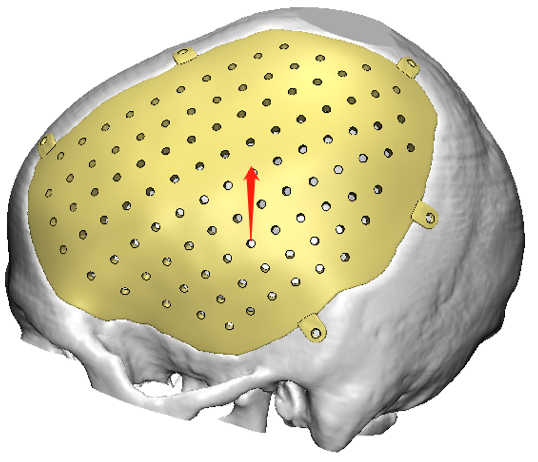

Paciente masculino, con un defecto de dimensiones aproximadas de 138.64×110.44mm el cual fue intervenido quirúrgicamente con excelentes resultados, un ejemplo de diseño con puente plano.